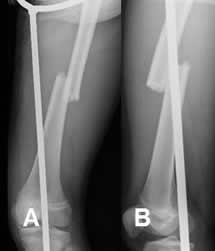

Fig 47. Fractura diastasada.

A: y B: Rx lateral. Fracturas conminutas, rotadas y diastasadas en las diáfisis femorales.